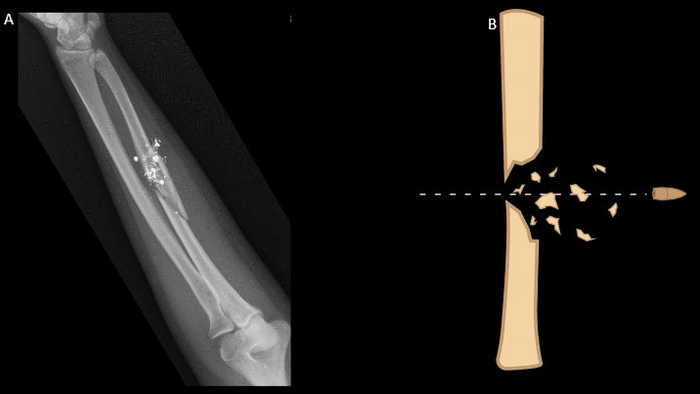

A. Comminuted, mild displaced spiral fracture of mid-shaft left radius with surrounding metallic and small displaced osseous fragments in surround soft tissue. B. Graphic demonstration fracture fragments and classical beveled appearance of fractured bone edges.